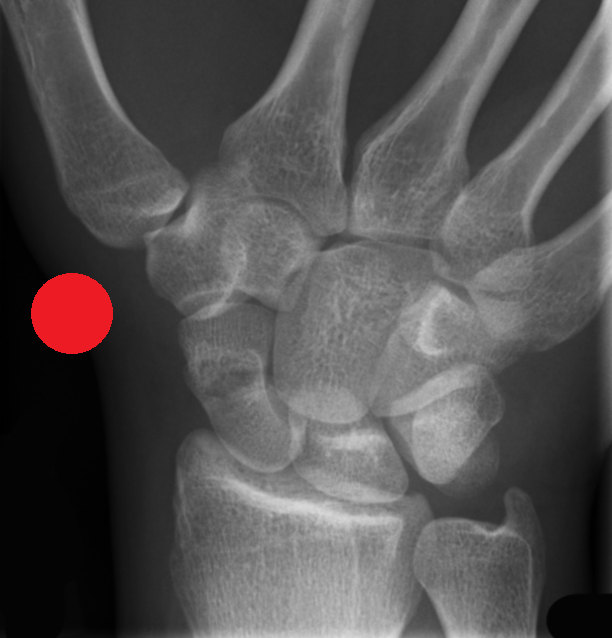

MSK CASES

www.mskradiology4u.co.uk

This TWO DAY comprehensive Red Dot X-Ray Interpretation Course includes Red Dot Trauma AND Red Dot Chest and is designed for Radiographers working in acute MSK care, for example in A/E or minor injuries and who are seeking to enhance confidence and improve their diagnostic assessment and accuracy.

The course focuses on the identification and escalation of suspected pathology, fractures, or other deviations from normal imaging appearances through case by case interogation, theory of image interpretation, logbook completion and image viewing assessment.

The course focuses on improving the skills needed to identify a range of acute pathologies on x-rays, including fractures, dislocations, chest abnormalities and more. The course will improve patient safety by reducing missed urgent findings, especially whilst waiting for report completion.

• Improved identification of key radiographic features of common acute pathologies, eg. fractures, dislocations, pnemothorax.

• Improved ability to distinguish between normal anatomical variants and common pathological findings on Radiographs.